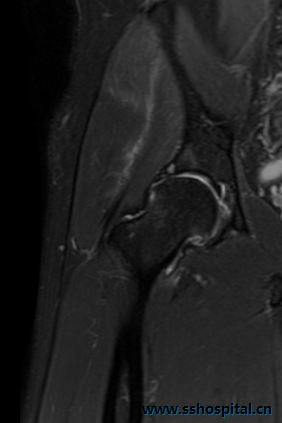

【中医特色疗法】髋关节反复疼痛?试试三氧治疗法

三氧治疗法具有激素的疗效,而无激素的副作用,可利用其抗氧化酶活性,改善微循环,促进机体对糖的利用,具有杀菌灭菌等特性,对炎症性关节疼痛具有良好的疗效。三氧还具有稳定性差的特性,30分钟左右即可分解成氧气,对机体具有营养作用。 吕生...